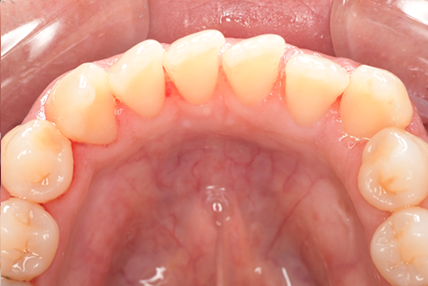

CASE 10

Before①

After①

Before②

After②

基本情報

| 年齢・性別 | 38歳・男性 |

| 主訴 | 下顎 歯石除去したい |

| 治療内容 | スケーリング |

| 治療期間 | 30分 |

| 治療費 | 約1,500円(保険診療) |

| リスク・副作用 | 知覚過敏、歯肉退縮 |

| 治療方針 | 歯肉縁上歯石を除去してから歯肉縁下歯石を除去します。ご自身でのプラークコントロールができるようになったら定期検診に移行します。 |

| 担当者所見 | 半年ぶりの歯科医院の受診。歯石が付きやすいためセルフケアの重要性をお伝えして、定期的にクリーニングを行います。出血率が高く炎症が強いため、今後はセルフケアを強化して歯周病治療を行います。 |